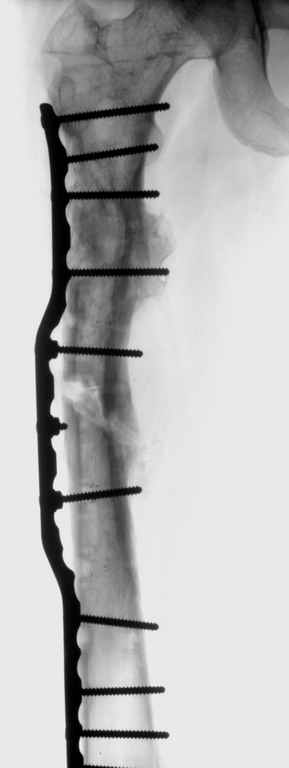

В ноябре этого года я обращался с просьбой о помощи в выборе тактики лечения больной с деформацией бедра на почве фиброзной дисплазии. Были получены интересные и очень полезные советы по операции.

Хотелось бы показать, что получилось в результате.

Операция выполнялась с помощью А.Н.Челнокова. Очень понравилась технология выполнения блокируемого остеосинтеза с использованием спицевого дистрактора, модифицированный гвоздь с латерализованным проксимальным отделом и возможностью многовинтовой фиксации проксимального и дистального участков бедра.